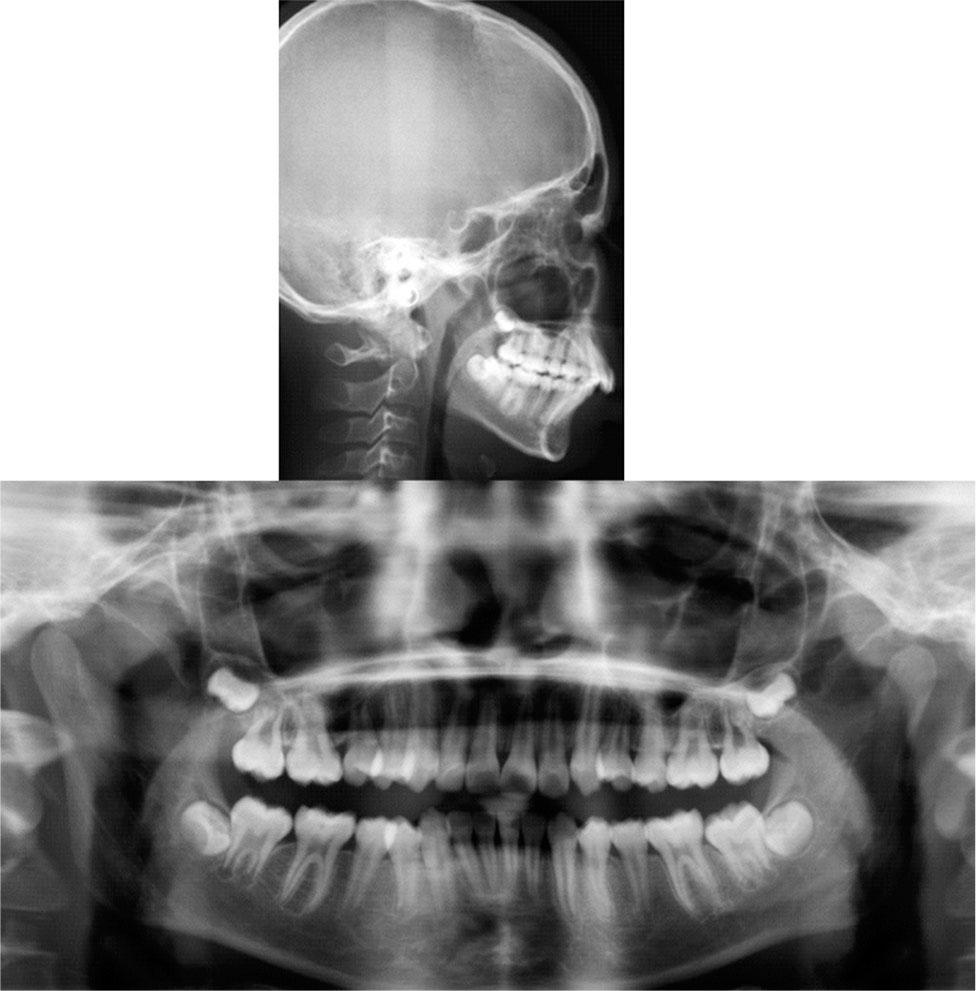

Figure 3.

Figure 4.